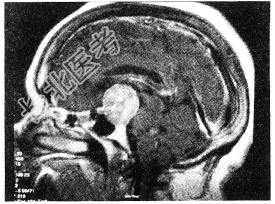

- 单项选择题垂体腺瘤(如图所示)首选的治疗方法应是